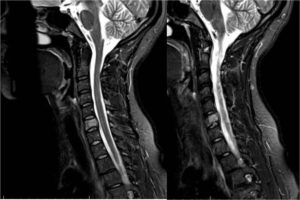

Видно ли остеохондроз на МРТ, и как именно?

Магнитно-резонансный томограф прекрасно показывает картину остеохондроза всех сегментов позвоночника. Куда большей информативностью в некоторых нюансах (именно в визуализации костной ткани) обладает только КТ (компьютерная томография).

Томограф позволяет выявить даже минимальные изменения в структуре позвоночного столба, поэтому имеется возможность заметить проблему на начальных этапах.

Магнитно-резонансная томография позволяет визуализировать различные патологические изменения, как общие, так и частные (свойственные определенным сегментам спины). При обследовании шейного отдела можно выявить следующие изменения:

- Компрессию (сдавливание) или повреждение позвоночных артерий дестабилизированными позвонками.

- Дегенеративно-дистрофические процессы (даже на начальных этапах).

- Патологический кифоз (в рамках осложнения длительно протекающего остеохондроза).

- Деформативные изменения позвонков шеи, их выпадение (спондилолистез, что нередко является спутником остеохондроза).